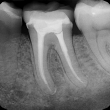

Out of nowhere, one of my molars turned on me. Before I knew it, I was sitting in a chair, mouth wide open, being told that my perfect record was about to be absolutely shattered.

Root canal. "No way...are you sure?" I asked, hoping, maybe, he meant a 'spa treatment' for my tooth. Nope. Root canal. (It's not cheap.) And, it was quite painful because the initial shots of novocaine did not deaden the nerve. This resulted in looking and speaking like a buccaneer at a Gala that evening.